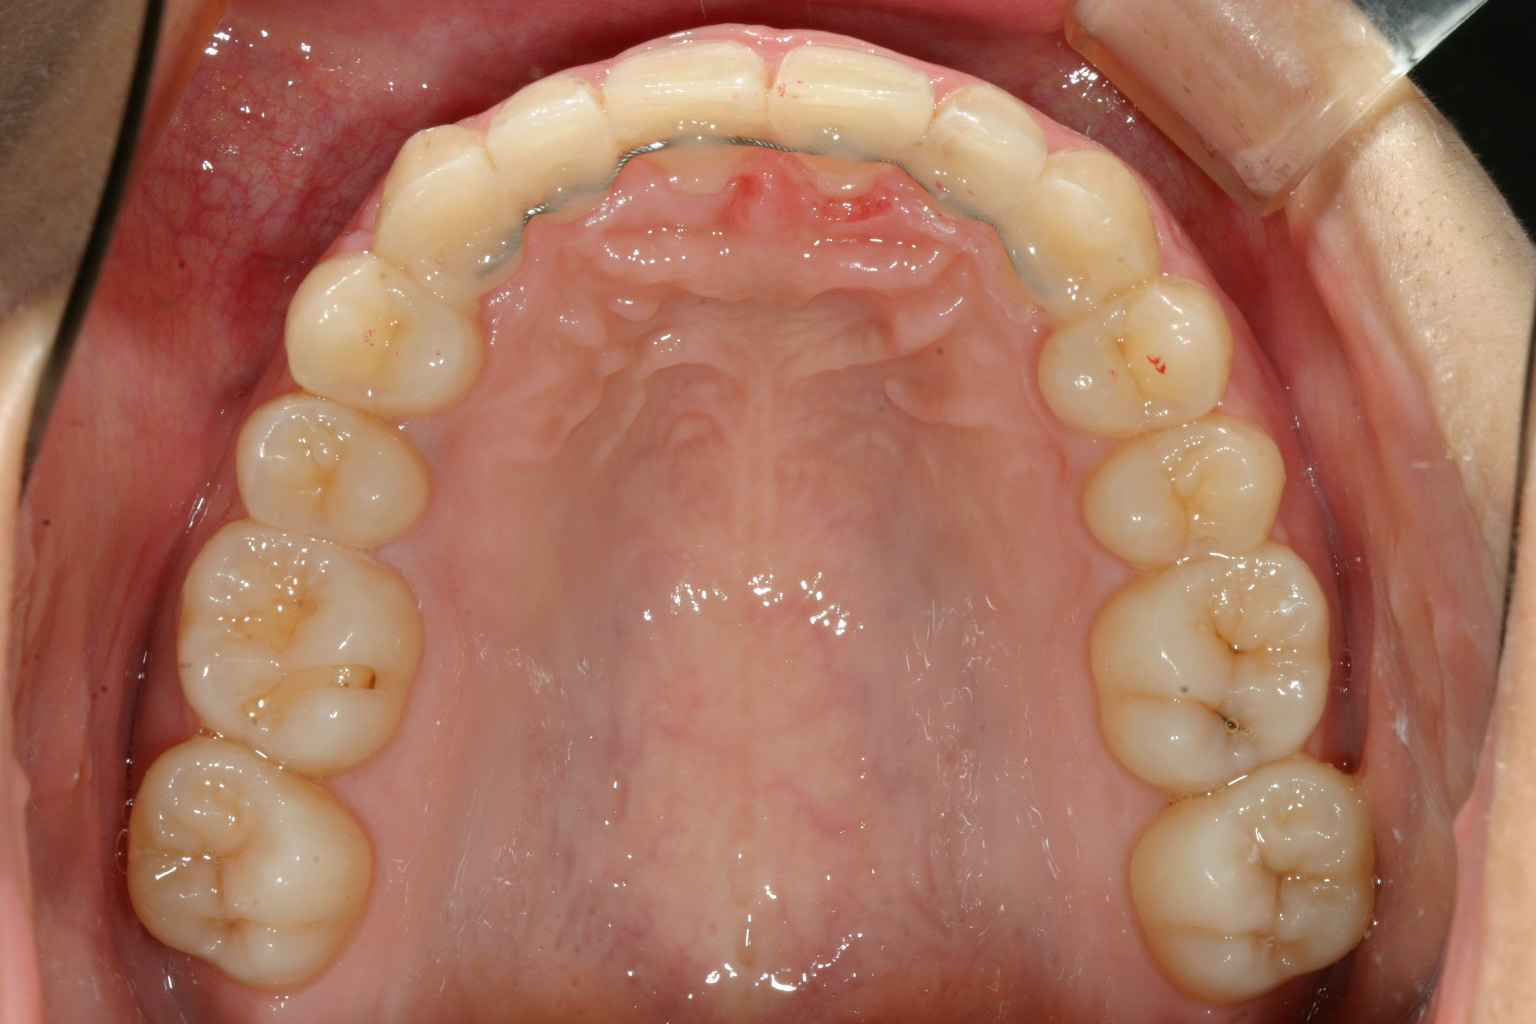

綺麗な歯並びが得られました。

下顎も凄い綺麗です。 beforeと比べてください。 U字形になってるのが分かります。 つまり犬歯と犬歯の間が開いたと言う事です。

オーバージェットもオーバーバイトも完璧です。